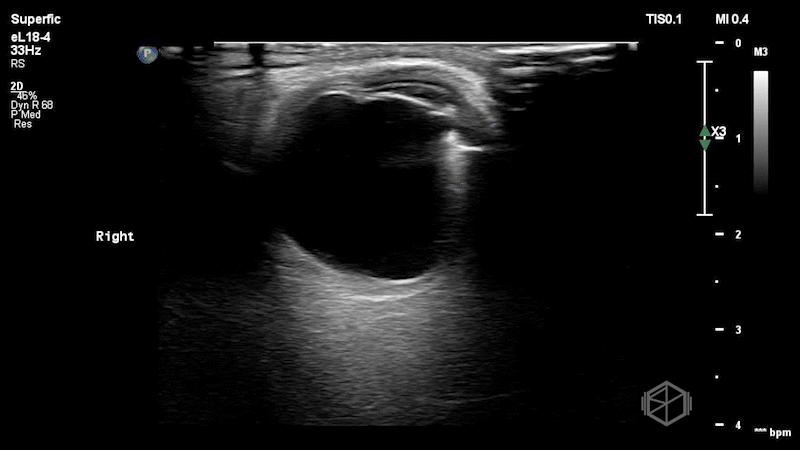

Eye Spy: POCUS Uncovers a Hidden Metallic Foreign Body